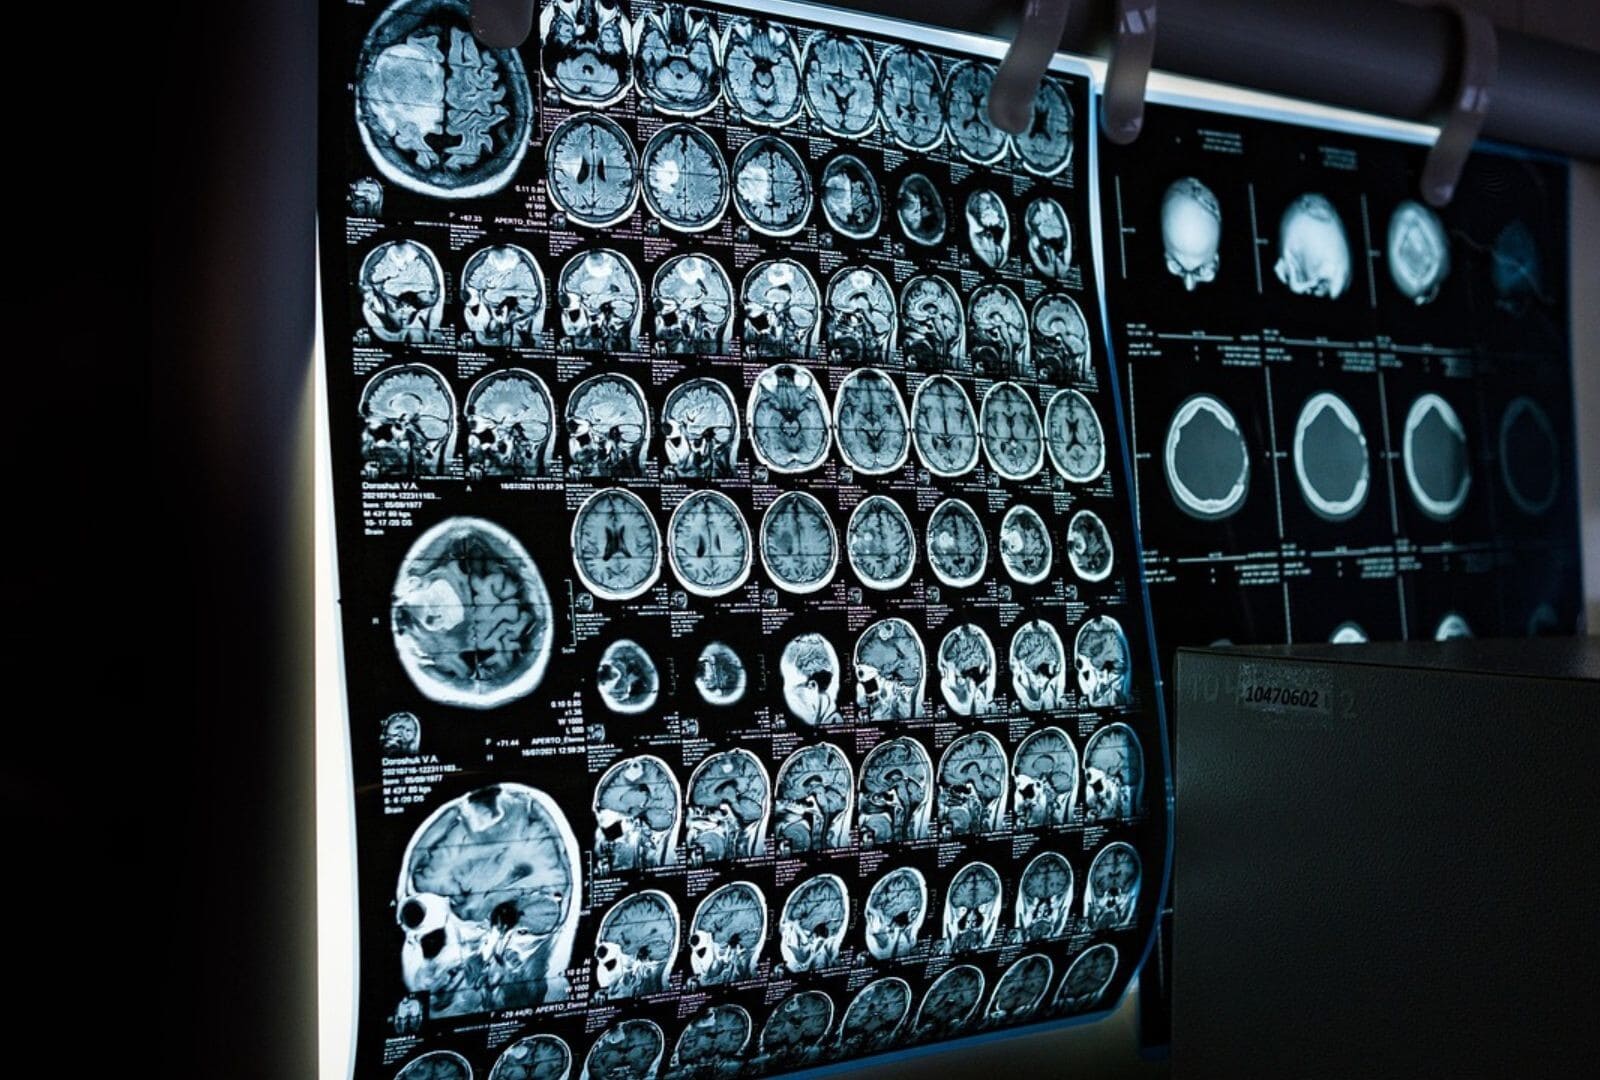

In May 2025, a new report titled The Cost to the UK Economy of Acquired Brain Injury, commissioned by the All-Party Parliamentary Group on Acquired Brain Injury and UKABIF, highlighted the profound economic and social impact of acquired brain injury (ABI). ABI can result from traumatic events such as accidents, as well as non-traumatic causes like stroke, encephalitis, meningitis, brain tumours, and hypoxia. The report estimates the total annual cost to the UK economy at £134.5 billion, covering direct healthcare costs, lost productivity, informal care, and most significantly the reduced wellbeing experienced across society.

ABI is often a complex, life-altering condition requiring coordinated, personalised rehabilitation from the earliest possible stage. Delays or inadequate access to specialist rehabilitation can lead to deterioration in physical and cognitive function, extended hospital stays, increased social care needs, and poorer long-term outcomes.

At STEPS Rehabilitation, we recognise that early, intensive rehabilitation is vital for maximising recovery following an acquired brain injury (ABI). We provide specialist, personalised programmes to a wide range of clients, including those, in a prolonged disorder of consciousness (PDOC), stroke survivors and those in rehabilitation for conditions like encephalitis or meningitis.